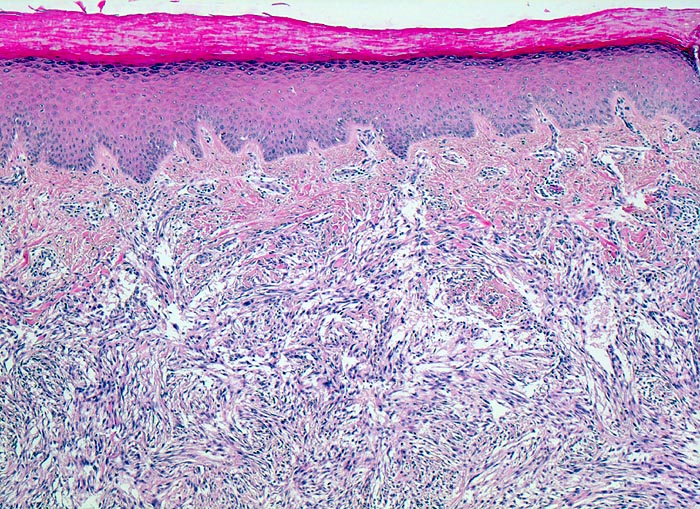

Zellreiches fibröses Histiozytom

Haut, Hand palmar, Finger

Die Epidermis zeigt eine leichte Hyperkeratose und Akanthose. Von der Epidermis durch eine schmale Kollagenfaserschicht abgegrenzt findet sich in der Dermis ein zellreicher spindelzelliger Tumor mit geflechtartig verwobenen Tumorzellbündeln.

Ploidie: Diploid, DNS-Index 1,9. S-Phasen-Fraktion: 19,4%, hoch. Das Messergebnis spricht für eine hohe proliferative Aktivität entsprechend einem zellreichen fibrösen Histiozytom.

Tumorrezidiv interdigital.